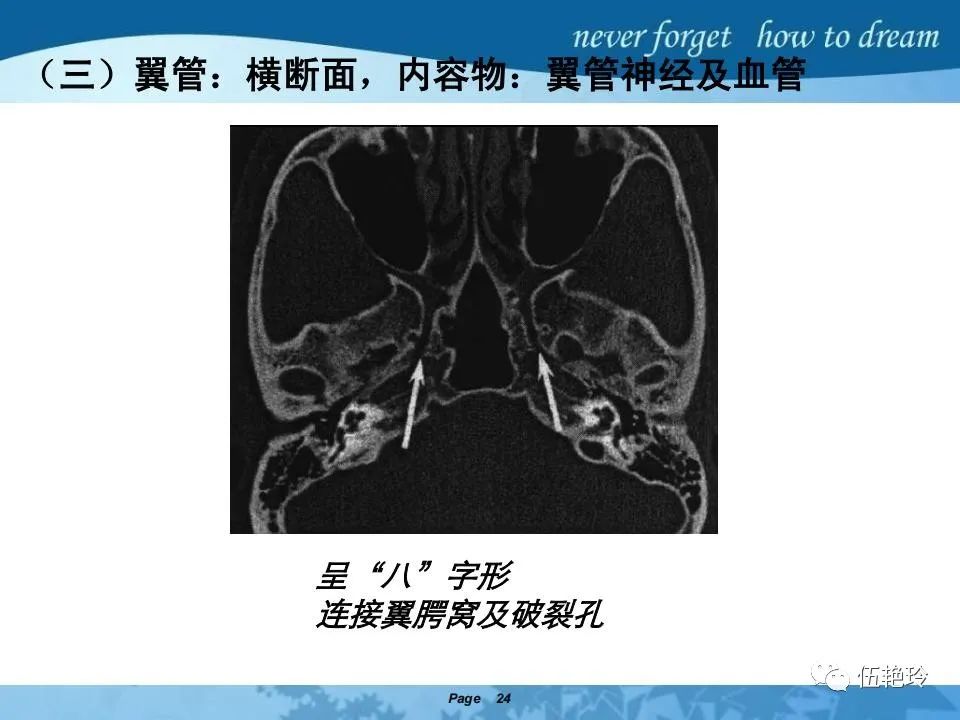

翼腭窝的解剖结构与鼻咽癌侵犯

2.31 向上颅内:①鼻咽顶壁→破裂孔(岩尖、斜坡)→蝶窦、海绵窦;②鼻咽顶壁→蝶骨基底部→蝶窦、海绵窦;③鼻咽侧壁→茎突前间隙→蝶骨大翼(卵圆孔)→海绵窦;④鼻咽侧壁→茎突前间隙→翼腭窝→ 颞下窝;⑤鼻咽前壁→鼻腔→翼突、翼腭窝→眶下裂→眶尖→海绵窦;⑥鼻咽前壁→鼻腔→上颌窦、筛窦;